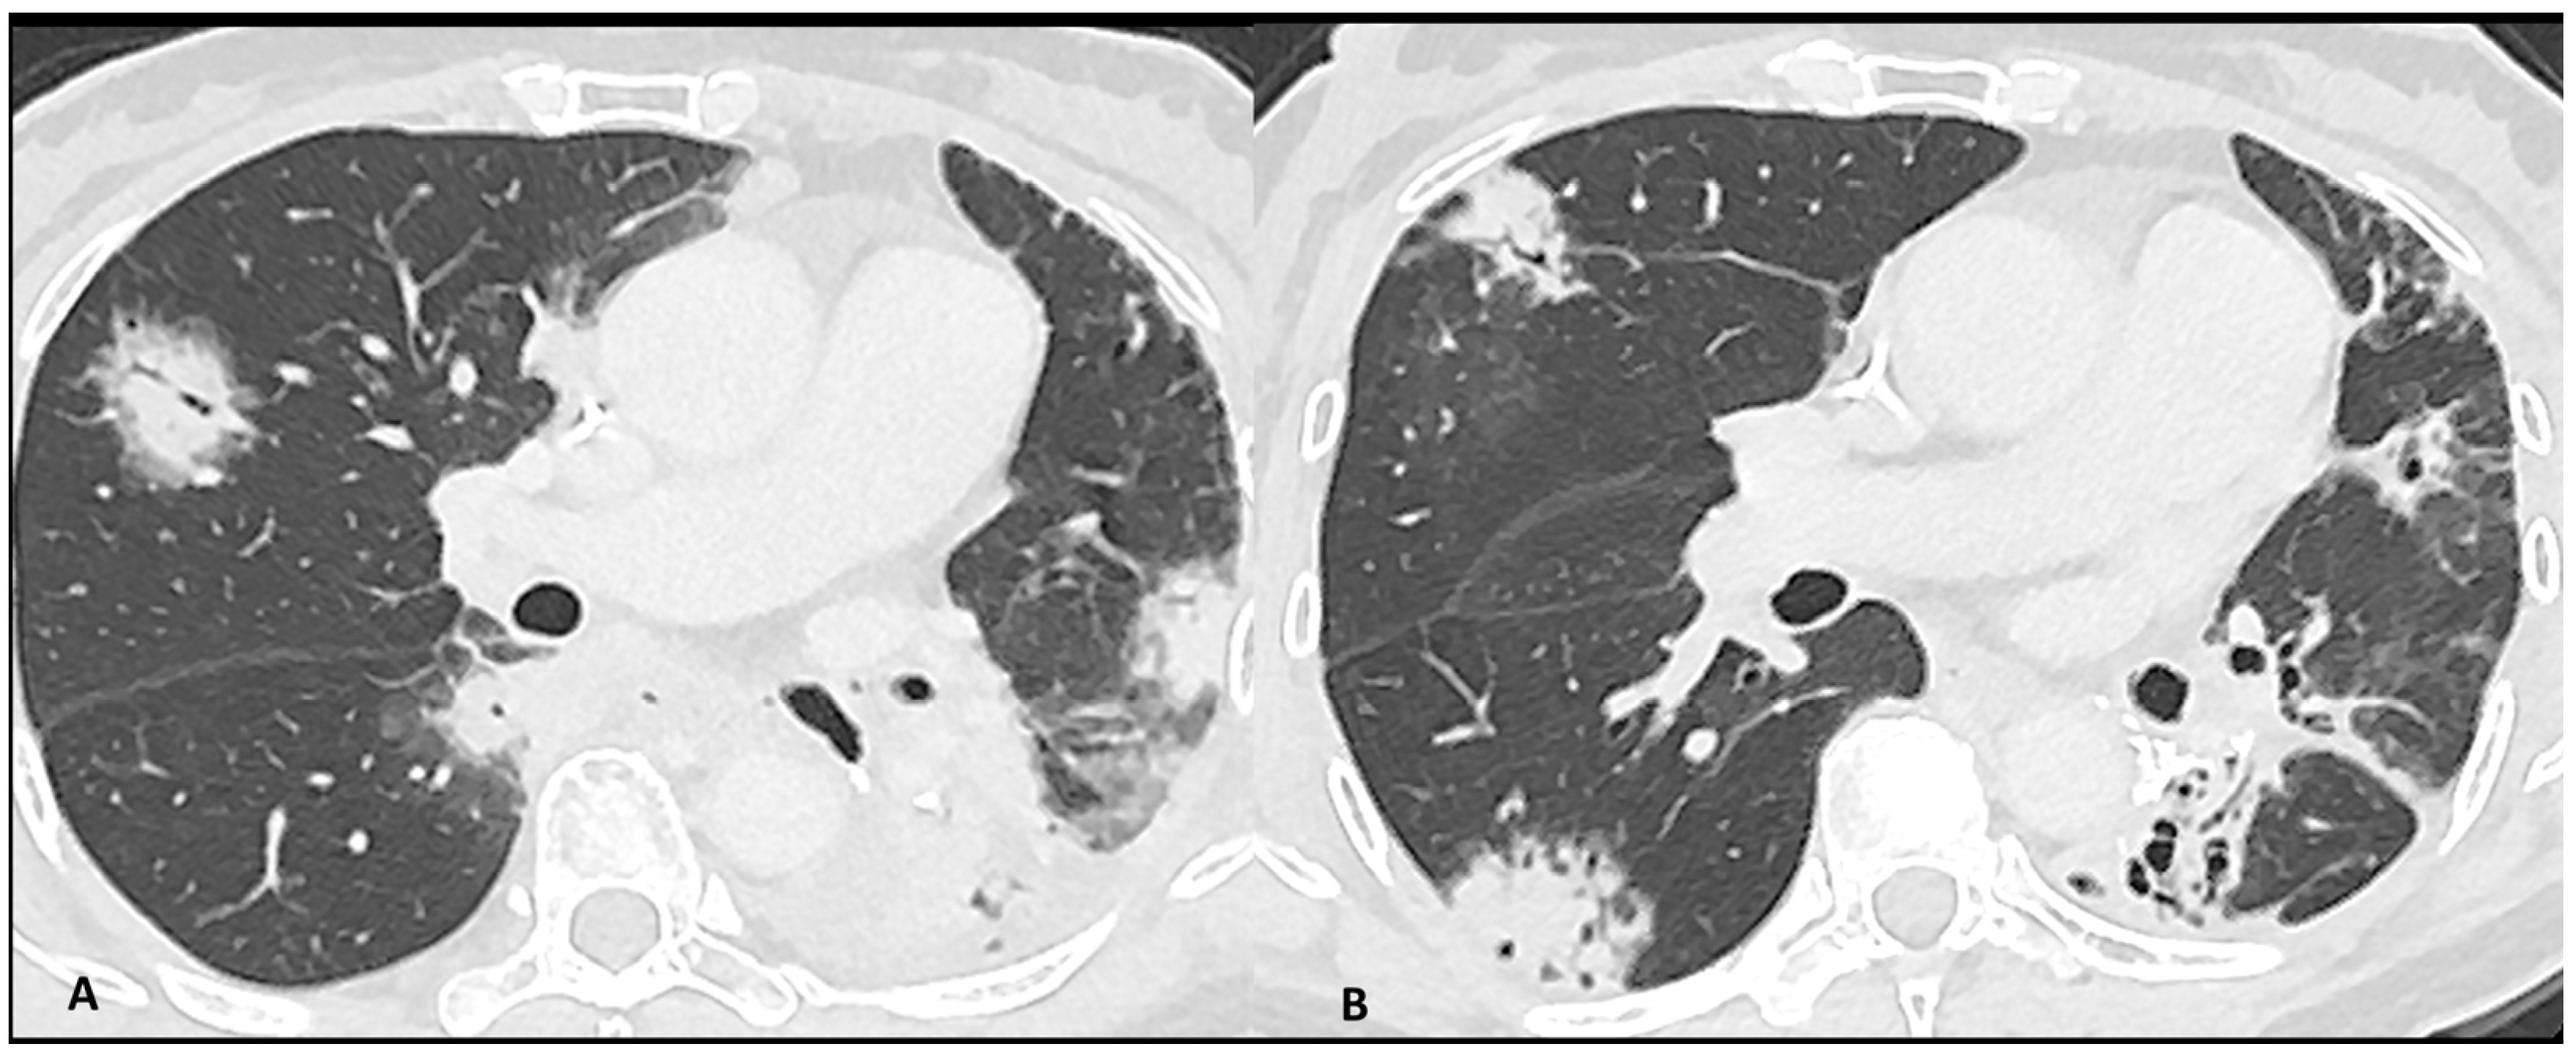

2.2.1. Ir-Pneumonitis

2.2.2. Sarcoidosis-Like Reaction

| Pneumonitis | OP | Multifocal, patchy, consolidations or GGOs with peribronchovascular and/or subpleural distribution | Migratory on a subsequent scan | Radiation Pneumonitis Infectious pneumonia Tumor progression |

| SPE | Scattered nodules or GGOs | Migratory and transient | Infectious Pneumonia | |

| HP | Bilateral and symmetric GGOs or poorly-defined centrilobular micronodules with upper lobes predominance and hypo-attenuated lobules | Expiratory acquisition to confirm the air-trapping in case of doubt | Infectious pneumonia (mainly viral and pneumocystis) Respiratory bronchiolitis | |

| NSIP | Bilateral and symmetric areas of GGOs +/− irregular reticulations, with peripheral and/or peribronchovascular distribution and lower lobes predominance. Bronchiolectasis and bronchiectasis often absent | Prone positioning acquisition to confirm the abnormalities in case of doubt | Infectious interstitial pneumonia (mainly viral and pneumocystis) Poor ventilation of dependent lung areas HP | |

| AIP/DAD | Bilateral dependent consolidation associated with GGO | Absence of reticulations and peribronchovascular thickening related to cardiac edema | Infectious pneumonia Cardiogenic oedema | |

| Bronchiolitis | Centrilobular nodules in tree-in-bud distribution | / | Infectious bronchiolitis | |